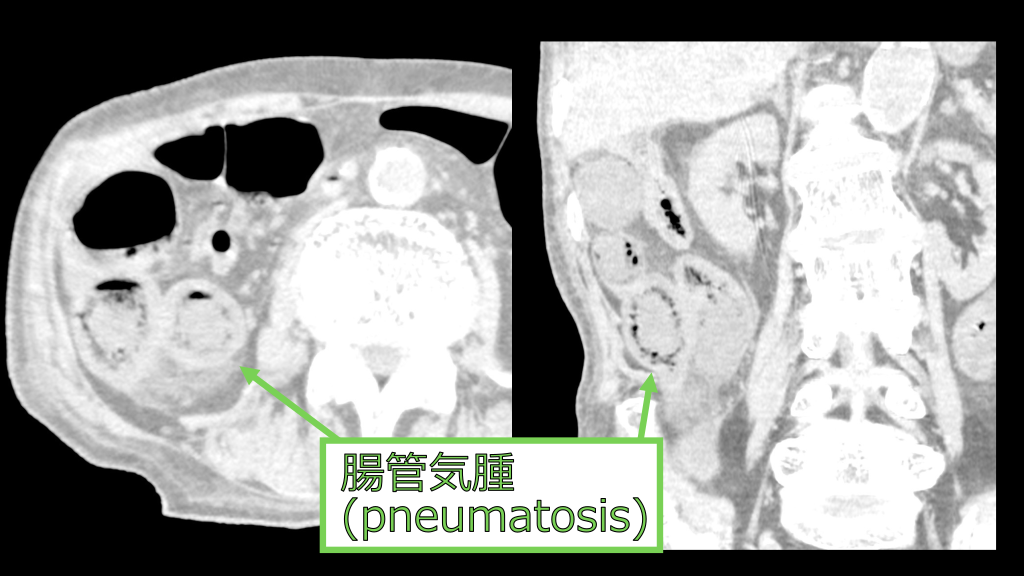

回盲部、⼩腸の壁の造影効果は減弱している